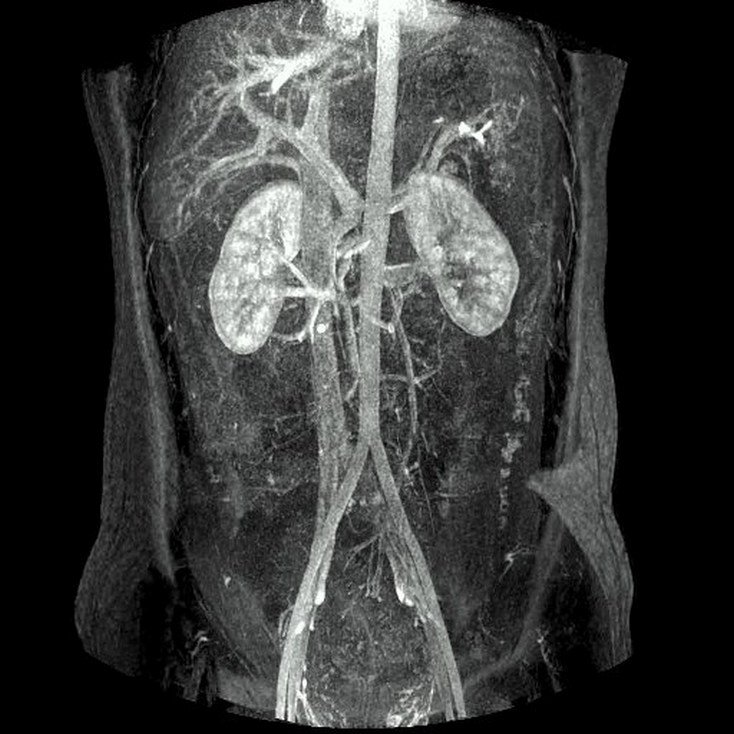

CT Kidney

Kidney Angiography